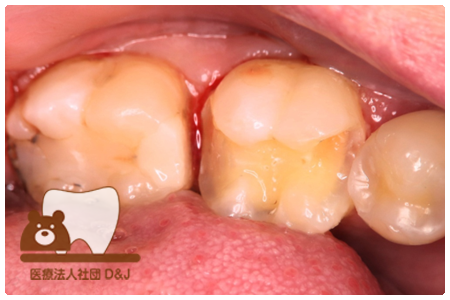

症例8フルジルコニアクラウン

治療前

治療中

治療後

29歳 女性

- 治療内容

- 銀歯からフルジルコニアクラウンへの修復

- 治療期間

- 根の治療含め3か月

- 費用

- 自費

フルジルコニアクラウン:77,000円(税込)

- その他の治療の費用は含まれておりません。

- リスク・副作用

- 強い衝撃が加わると欠けたり割れたりする可能性があります。また、噛み合わせの状態によっては脱離や周囲の歯への影響が出ることもあります。